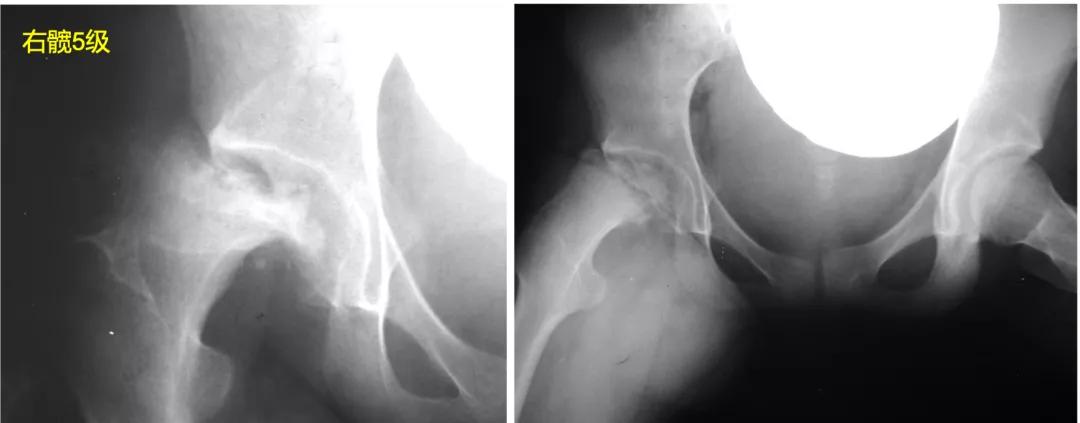

S5:股骨头扁平塌陷严重,头臼不匹配。

Stulberg分级将髋关节是否匹配总结为:①球形适配(1 级、2 级),不易发生骨关节炎;②非球形适配(3 级、4 级),成人时会有轻中度骨关节炎;③非球形非适配(5 级),50 岁前即出现严重骨关节炎。所以,对于儿童期Perthes病的治疗,我们应该尽量避免股骨头变形、头臼不匹配,追求Stulberg1、2级的结果。